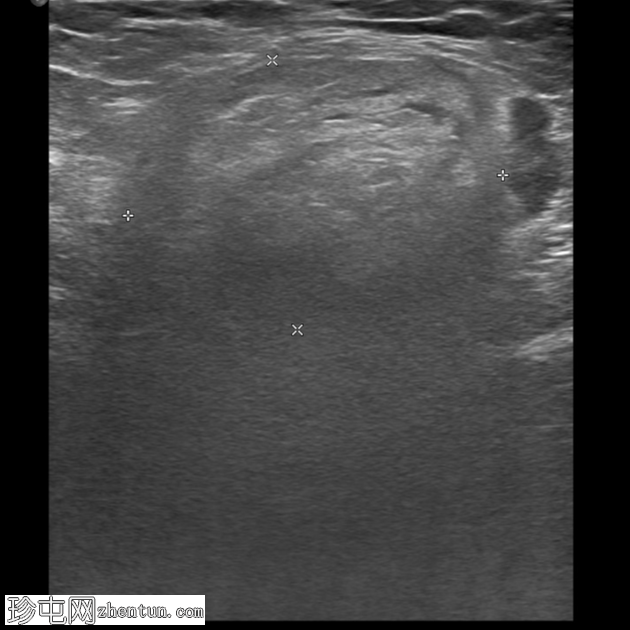

冠状C+门静脉期

右腹股沟疝,内含脂肪。疝颈位于下腹壁动脉起点下方。疝囊压迫股总静脉。脂肪含量不均质,脂肪条带状排列,并有微量液体,提示为嵌顿性股疝。

可见少量腹股沟淋巴结轻度肿大。